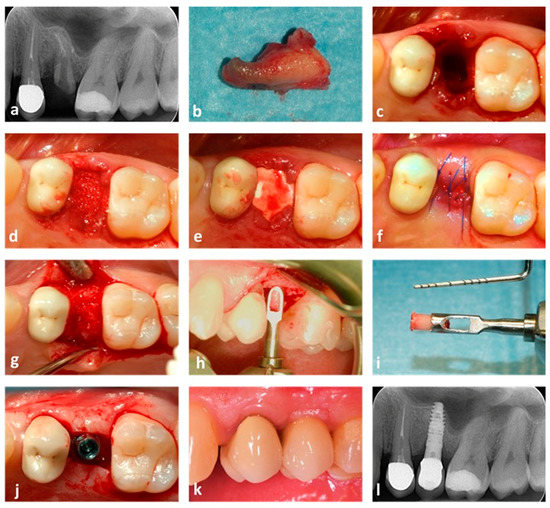

2.4. Surgical Procedure